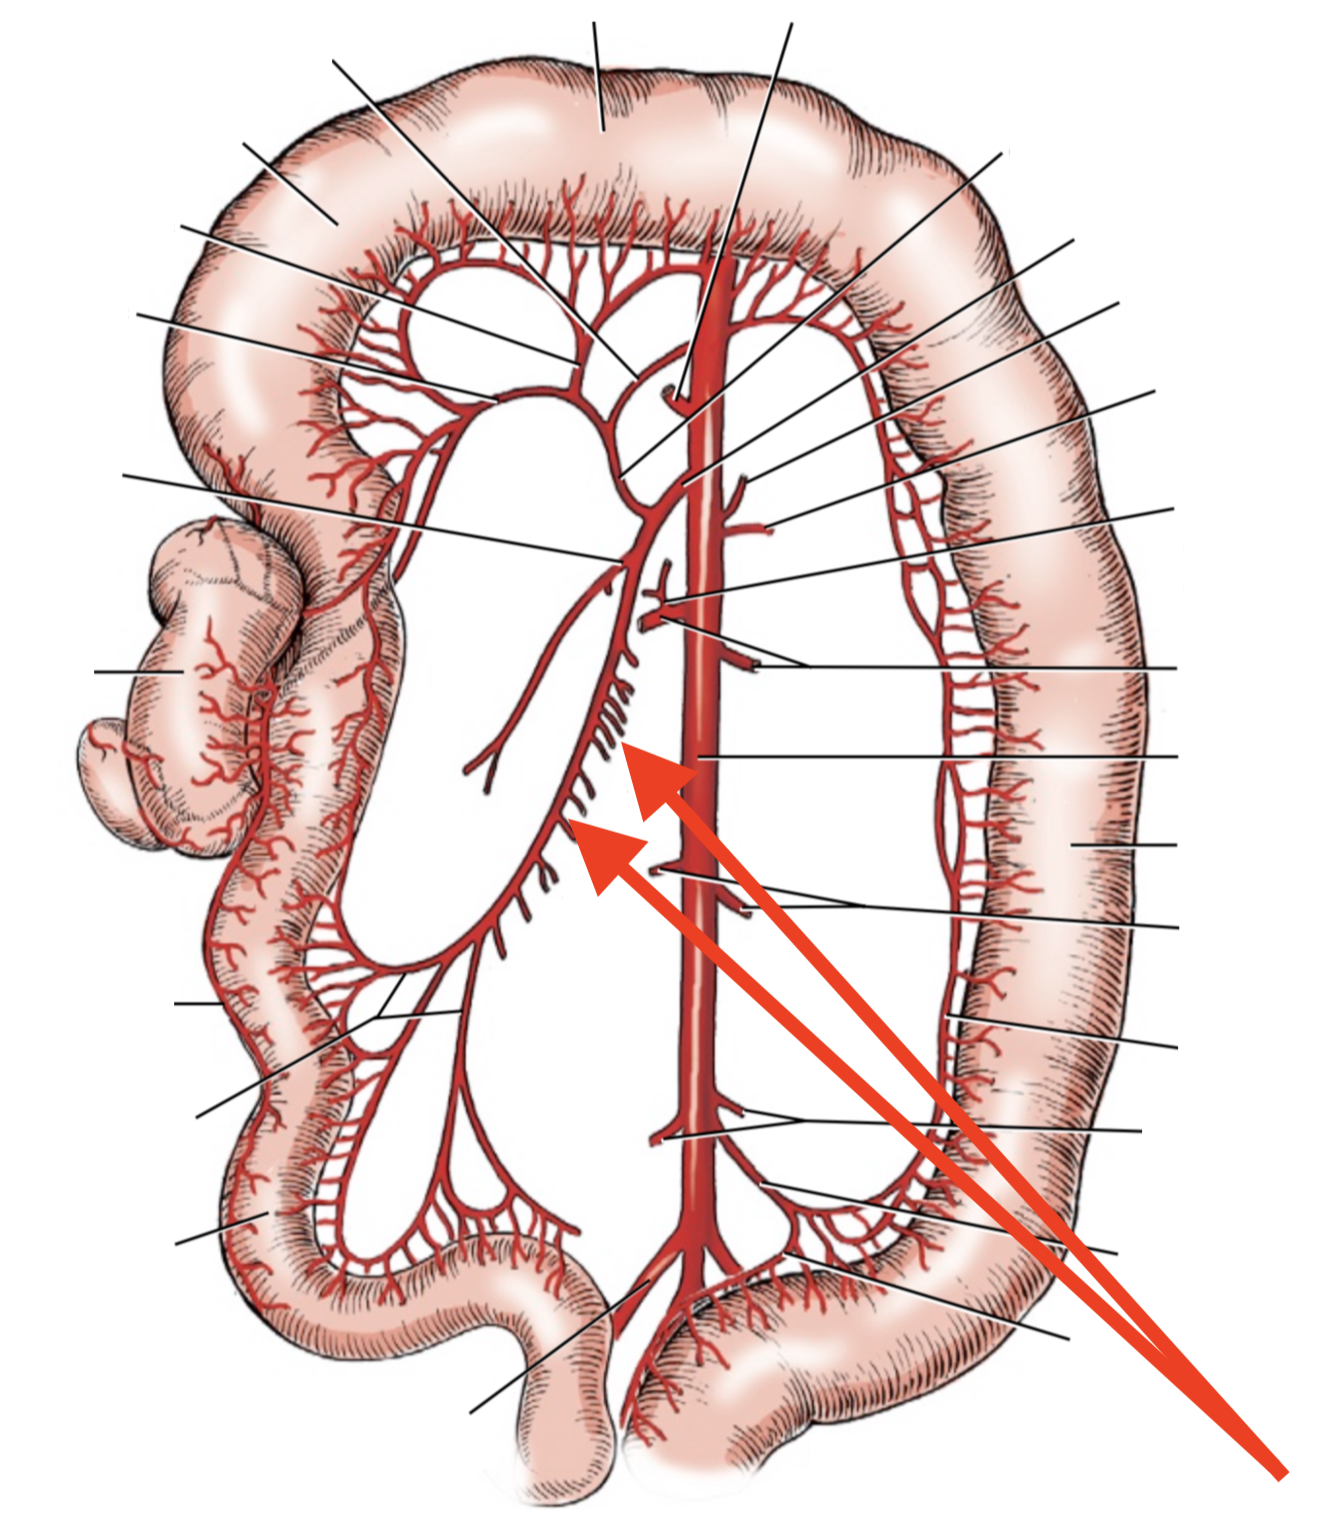

A

A. mesenterica cranialis

15

Q

A

A. pancreaticoduodenalis caudalis

16

Q

A

Aa. jejunales

17

Q

A

A. ilei

- Anastomises with r. ileus mesenterialis a. iliocolica

18

Q

A

A. ileocolica

19

Q

A

A. colica dextra

20

Q

A

A. colica media

21

List the branching of *a.* *mesenterica* *caudalis*

* *A. colica sinistra*

* *A. rectalis cranialis*

List the branches of *a.* *mesenterica* *cranialis*

* *A.* *pancreaticoduodenalis* *caudalis*

* *Aa. jejunalis*

* *A. ilei*

* Common trunk

* A. colica media

* A. colica dextra

* *A. ileocolica*

* *R. ilei mesenterialis*

* *A. cecalis*

* *R. colicus*